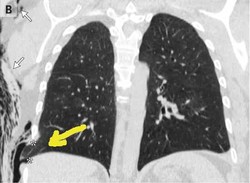

Perawatan kanker payudara dari tahun 1950 terus mengalami kemajuan. Dengan metode pencegahan melalui skrining dan mamografi, ternyata masih belum efektif.